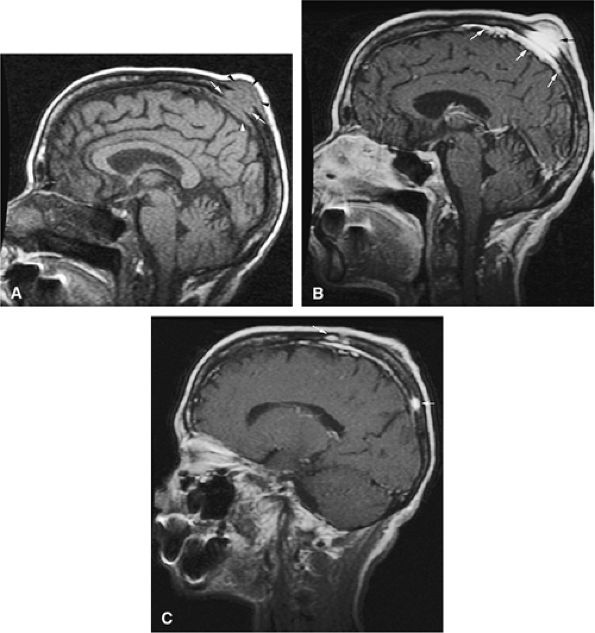

FIGURE 13.57 ● Extensive bone marrow replacement of the skull secondary to metastatic renal cell cancer (arrowheads). Large focal lesions with intracranial extension are present (arrows). (A) Axial proton density-weighted image shows expansion of the marrow cavity and metastatic deposits that demonstrate intermediate signal intensity. (B) Extensive enhancement of metastatic disease is seen on an axial fat-suppressed T1-weighted image following the intravenous administration of gadolinium.

FIGURE 13.58 ● Colon carcinoma metastatic to the pelvis (arrows) demonstrates high signal intensity on coronal (A) and axial (B) STIR images. (C) Enhancement of metastatic deposits is noted on a corresponding coronal fat-suppressed T1-weighted image following intravenous administration of gadolinium. Metastatic deposits are better visualized on the STIR sequence.